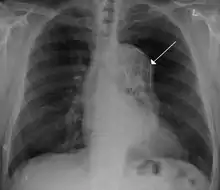

A thoracic aortic aneurysm is an aortic aneurysm that presents primarily in the thorax.

A thoracic aortic aneurysm is the "ballooning" of the upper aspect of the aorta, above the diaphragm. Untreated or unrecognized they can be fatal due to dissection or "popping" of the aneurysm leading to nearly instant death. Thoracic aneurysms are less common than an abdominal aortic aneurysm.[2] However, a syphilitic aneurysm is more likely to be a thoracic aortic aneurysm than an abdominal aortic aneurysm. This condition is commonly treated via a specialized multidisciplinary approach with both vascular surgeons and cardiac surgeons.

Treatment

The size cut off for aortic aneurysm is crucial to its treatment. A thoracic aorta greater than 4.5 cm is generally defined as aneurysmal, while a size greater than 6 cm is the distinction for treatment, which can be either endovascular or surgical, with the former reserved for pathology at the descending aorta.[13]

Indication for surgery may depend upon the size of the aneurysm. Aneurysms in the ascending aorta may require surgery at a smaller size than aneurysms in the descending aorta.[14]

Treatment may be via open or via endovascular means.